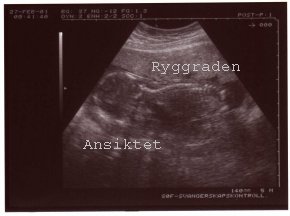

Ultralydsundersøkelse #1

Tirsdag 27.februar 2001 var jeg til ultralydsundersøkelse på SØF. Jordmoren var ok. Fant ut at morkaken lå på livmorens fremre vegg, men at den var trukket opp. Dessuten fant hun ut at jeg kun var 15+3 og ikke 17+6. Fikk flyttet terminen fra 8.aug til 20.aug. Greit nok. Fikk med oss to fine bilder og ny timeavtale tirsdag 20.mars. Gleder meg til å se hvor stor mininurket er blitt da! Skal også sjekke om morkaken har trukket seg enda lenger opp.